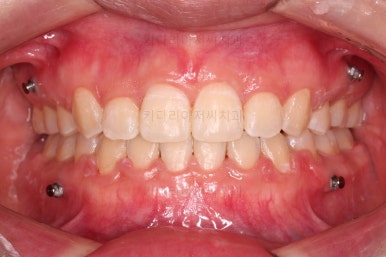

치열이 매우 바르게 되었고 교합도 양호하며 뻗쳐 있던 앞니 각도도 좋아졌네요.

돌출의 느낌도 처음보다 많이 좋아졌어요.

웃을 때 보이는 치열의 느낌도 좋고요.